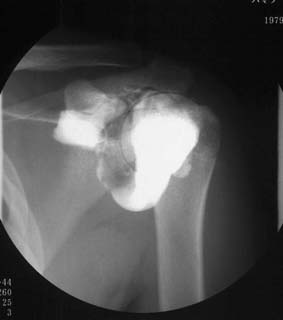

関節腔造影

肩、膝、足関節等の関節を構成する関節腔内の構造物、周囲の軟部組織の状態を知るための検査です。

注射針にて関節腔を穿刺し関節内液内に造影剤・空気を注入して関節を動かしながら撮影を行います。

肩関節腔造影